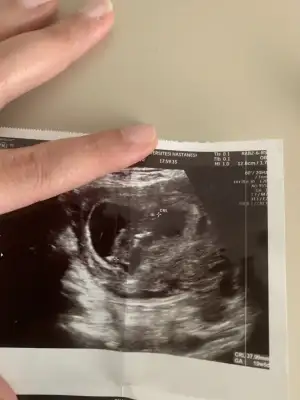

Benimkinede bakar mısınız?

• 5C265605-6959-4271-A39F-D6822F53D3A5.webp

5C265605-6959-4271-A39F-D6822F53D3A5.webp